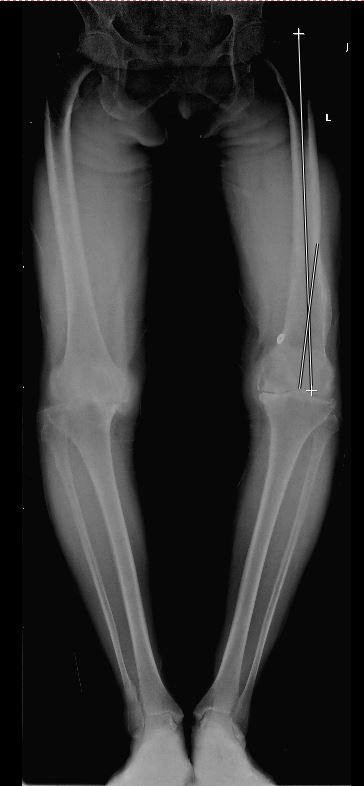

2018年6月1日,我院骨五科钱宏主任团队,率先完成我院首例3D打印技术辅助下股骨畸形全膝关节置换术,并获得成功。 患者女性,60岁,20年前曾有股骨髁上骨折病史,后骨折畸形愈合,畸形愈合后股骨远端存在屈曲以及内翻畸形。如果按照常规方法行膝关节置换,股骨定位会存在较大偏差,有可能因为股骨截骨偏差导致下肢力线不良以及软组织不平衡。术前钱宏主任经过慎重考虑,决定采用3D打印定制个性化截骨导板,精确截骨,避免常规截骨偏差可能造成的不良后果,使用3D技术需要对患者行全下肢CT平扫,同时在计算机内重新建模并模拟截骨,并根据截骨后结果计算力线,评估截骨后结果,并计算出假体型号,经过一系列充分的术前规划,并利用3D打印技术打印出患者股骨以及胫骨模型,股骨以及胫骨截骨导板。 在术中,利用3D打印制作的截骨导板,在导板引导下进行截骨,做到了手术操作的完全准确,在保证手术质量的前提下,缩短了手术时间,降低了患者风险。 随着3D打印技术的成功应用,标志着我院骨科针对复杂的膝关节置换的水平达到了一个新的高度。(苏希国 朱步奇)

与对侧股骨对比,患者左侧股骨存在内翻畸形 重建后的股骨3D模型与模拟力线